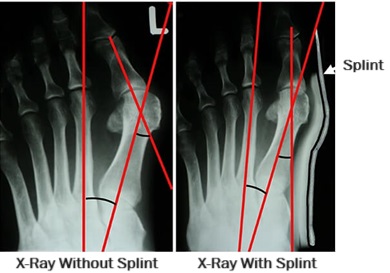

Bunion splints essentially work in one of two ways, some combining both. Firstly, they can help correct the deformity at the toe, bringing it back into a normal position. This prevents stiffness and tightness developing in the joint and surrounding soft tissues, relieving symptoms and helping to stop the progression of the toe deviation.